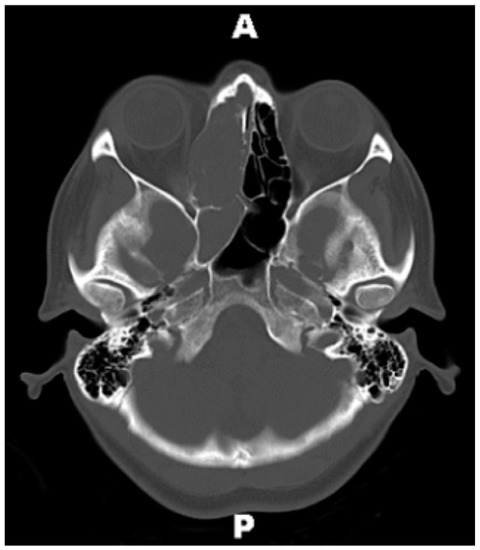

Figure 1. Prehospitalization computed tomography scan (CT) Brain without Contrast, axial view. Initial CT obtained by primary care physician, which demonstrates complete opacification of the right ethmoid and sphenoid sinuses. Abbreviations: A = anterior; P = posterior.